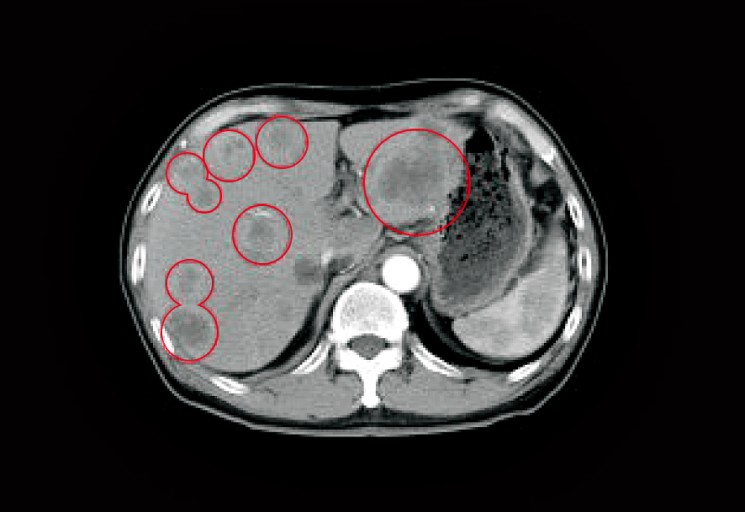

- **정밀검사(복부 CT, MRI, 초음파 내시경 등)**로 조기 발견이 가장 중요합니다.